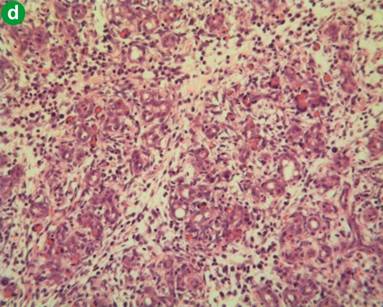

H&E preparations of pancreatic parenchyma in the control group is shown in Figure 4a. Induction of pancreatitis was associated with diffuse injury characterised by oedema, polymorphonuclear leukocyte infiltration and acinar cell disruption. There were also areas of haemorrhage and necrosis (Figure 4b). Xigris® given prior to induction was associated with a significant reduction in the degree of pancreatic injury (Figure 4c). In contrast, Xigris® administered after induction of acute pancreatitis was associated with similar patterns of injury to the acute pancreatitis group (Figure 4d). There was no associated increase in pancreatic parenchymal haemorrhage in either group receiving Xigris®. Histological injury scores were significantly different among groups (P<0.001; Kruskal-Wallis). Post-hoc analysis with Bonferonni adjustment revealed higher scores in the acute pancreatitis group in comparison to both control and the group receiving Xigris® prior to induction of acute pancreatitis (control vs. acute pancreatitis: P=0.001; acute pancreatitis vs. Xigris® pre-acute pancreatitis: P=0.004; Mann-Whitney) (Figure 5). Scores in the acute pancreatitis group differ significantly from the Xigris® post-acute pancreatitis group (P=0.039; Mann-Whitney). With reference to haemorrhage there was no significant difference among groups (P=0.196; Kruskal-Wallis) (Figure 6).

Figure 4. H&E preparations of pancreatic parenchyma in the four groups. a. Representative control animal (original magnification x10). b. Representative L-arginine-induced acute pancreatitis animal. Note extensive disruption of acinar architecture with necrosis and haemorrhage (original magnification x10). c. Animal pre-treated with Xigris®. Note in particular the preservation of acinar cell architecture and the absence of haemorrhage (original magnification x40). d. Animal treated with Xigris® after the induction of pancreatitis. Note extensive disruption of acinar architecture, oedema and inflammatory cell infiltrate (original magnification x10). |